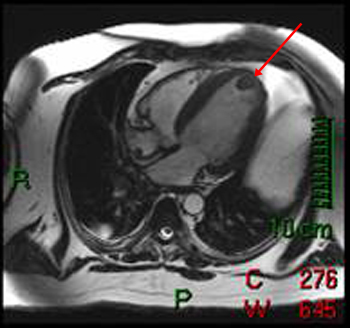

Answer: D. Stanford Type A Aortic Dissection. This image shows a dilation of the ascending aorta with a normal caliber descending aorta. An intimal flap can clearly be seen in the ascending aorta (arrow) representing an aortic dissection. There is no wall thicken to suggest an intramural hematoma. This aortic dissection is Stanford Type A since it includes the ascending aorta; Type B would include only the descending aorta. Somner T, Freshke W, Holzknecht N et al. Aortic dissection: a comparitive study of diagnosis with spiral CT, multiplanar transesophageal echocardiography, and MR imaging. Radiology 1996; 199(2): 347-52.17) What abnormality is seen on the T1-weighted (left) and T2-weighted (right) images below? ![]() Answer: A. Pericardial Cyst. These images show a homogenous mass (arrowheads) in the right cardiophrenic angle that is adherent to the pericardium and has relatively high signal on T2-weighted images and relatively low signal on T1-weighted images. The signal characteristics and cardiophrenic location are classic for a pericardial cyst. A lipoma would have signal characteristics that mirror subcuanteous fat. A myxoma would be within the heart itself. A pericardial mesothelioma would be more heterogenous. Constrictive pericarditis normally appears as a thickening of the pericardium, but these images clearly show a mass. Breen, JF. Imaging of the Pericardium. Journal of Thoracic Imaging 2001; 16(1): 47-54.18) This image is most consistent with what diagnosis? ![]() Answer: C. Amyloidosis. This image shows DHE sparing the subendocardium in a somewhat patchy distribution (arrows); this is most consistent with amyloidosis. There is no pericardial thickening to suggest constrictive pericarditis. Transmural and subendocardial infarctions would have DHE in a coronary artery distribution. VSD would demonstrate a connection between the ventricles. Maceira AM, Fisher NG, McKenna WJ, Pennell DK, et al. Cardiovascular magnetic resonance in cardiac amyloidosis. Circulation 2005; 111(2): 186-93.19) What abnormality is seen in the sagital view below? ![]() Answer: C. Aneurysm of the aortic root. This image shows a fusiform aneurysm of the aortic root (arrows) in a patient with Marfan�s syndrome. Additionally, there is loss of the distinctness of the sinotubular junction (arrowheads), a common finding in patients with Marfan's syndrome. Compare with the normal aorta in the image to the right (coronal image). These patients need periodic examinations to determine the necessity of prophylactic surgery to prevent aortic dissection. There is no intimal flap seen, so the patient has not yet suffered a dissection. Fattori R, Bacchi Reggiani L, Pepe G, Napoli G, Bna C, Celletti F, Lovato L, Gavelli G. Magnetic resonance imaging evaluation of aortic elastic properties as early expression of Marfan syndrome. Journal of Cardiovascular Magnetic Resonance 2000; 2(4): 251-6.20) What abnormality is seen in the DHE image below? ![]() Answer: C. Microvascular obstruction. There is a focus of unenhanced subendocardium (arrow) surrounded by transmural DHE in the anteroseptum. This unenhanced subendocardium represents an area of microvascular obstruction (MO) within a transmural infarction. Gadolinium contrast media cannot enter an area of MO because the vessels are destroyed. Wu KC, Kim RJ, Bluemke DA, et al. Quantification and time course of microvascular obstruction by contrast-enhanced echocardiography and magnetic resonance imaging following acute myocardial infarction and reperfusion. Journal of American College of Cardiology 1998; 32:1756-1764. |